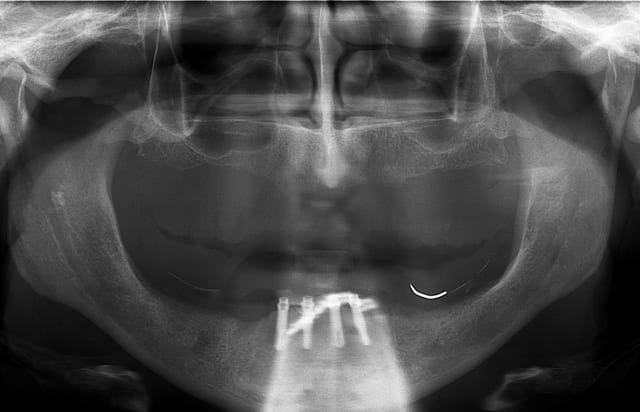

merci Thomas je suis bien rentré (croisé 6 paires de "jumelle" avec des habits bleus, mais à chaque fois coup de bol...)et je ne résiste pas au plaisir de passer le pano de notre ami.

Bien sur c'est du travail "d'amateurs", les axes sont nuls mais il semblerait que ton patient va l'avoir son amovo-inamovible!

Dis donc ce cas est une "pure merveille"

D où tu le sors et quelle littérature soutient un pareil traitement??????

y'en a même une sur l'OPT n°2 !!!